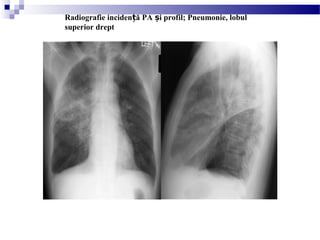

Radiografie inciden ă PA i profil; Pneumonie, lobulț ș

superior drept